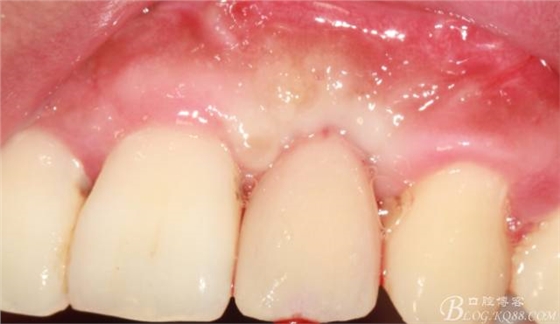

10天拆線一切正常,又過了兩周患者復(fù)診,自述期間無異常??趦?nèi)檢查,真的嚇了一跳,唇側(cè)鼓了個包,擠壓有白色分泌物溢出,絕對不是膿液,液體排除后,術(shù)區(qū)觸診空虛,外觀塌陷。這時候考研大夫的時刻到了,是先觀察一段時間再說?還是馬上進(jìn)行處理?我的回答是:馬上處理!如果你沒有及時處理,而是放患者回家觀察,那么接下來會發(fā)生如下情況:1.回家后患者家屬及親友會有很多你可以想象得到的討論;2.患者及家屬會對你產(chǎn)生不信任,勢必會到其他門診或醫(yī)院檢查,他院大夫會不會發(fā)表對你不利的言論;3甚至?xí)蚁嚓P(guān)法律界人士找你討要說法。

于是我果斷告知患者,手術(shù)失敗了,不能拖延,如不及時處理,炎癥繼續(xù)發(fā)展會很快波及鄰牙牙槽骨。患者接受我的建議。切開翻瓣,骨粉及生物膜消失了,骨吸收嚴(yán)重,幸運的是,因為處理及時,鄰牙骨支持依然存在。

事實證明,我的做法沒有錯誤,一個月后,軟組織健康愈合。鄰牙軟組織沒有退縮。